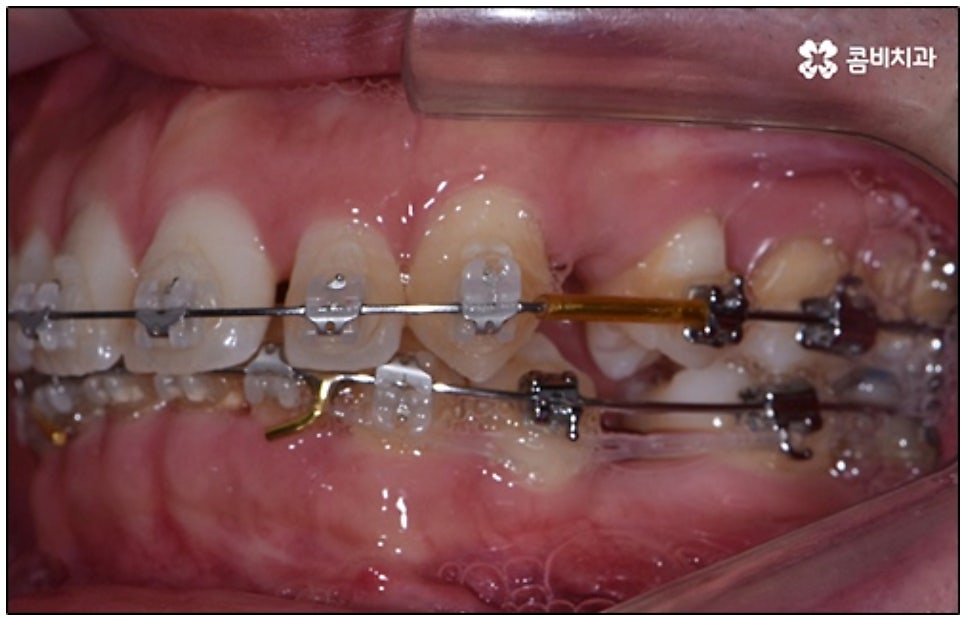

요즘 가장 많이 쓰이는 것은 클리피씨교정 장치로, 브라켓에 자체적으로 여닫을 수 있는 클립(뚜껑)이 있어 보다 손쉽게 와이어를 장착하거나 제거할 수 있어요. 이와 같은 자가 결찰 방식을 이용하게 되면 미세 철사로 일일이 와이어를 잡아주지 않아도 되기 때문에 장치로 인한 불편함이나 통증이 줄어들 수 있는데요. 뿐만 아니라 관리를 위해 치과에 내원하여 진행 상황에 맞게 새로운 와이어로 교체하고 교정력을 걸어주는 데 걸리는 시간 역시 단축되며, 상황에 따라 내원 횟수 자체를 줄여줄 수도 있어 방문 시간을 내는 것이 자유롭지 않은 군인분들이나 직장인분들도 치료할 수 있어요.

또한 클리피씨교정 장치는 심미성이 높기 때문에 많은 분들이 선호하고 있는데요. 클립이 달린 세라믹 (cilppyC-Ceramic의 약자) 이라는 뜻을 가진 이름에서 알 수 있듯이 클리피씨교정 장치는 브라켓 소재가 치아 색상과 비슷하여 눈에 잘 띄지 않으며 내구성이 좋고 크게 변색 되지 않는다는 장점을 가지고 있어요.

말씀드린 것과 같은 다양한 이점들이 있기 때문에 현재 본원의 교정 환자분들은 대부분 클리피씨교정 장치를 이용하여 치료를 진행하고 있습니다. 사진 역시 돌출입 교정을 위해 발치 후 클리피씨교정 장치를 이용하신 환자분의 케이스인데 시간이 지날수록 점차 앞니가 자연스럽게 들어가고 위아래 교합이 정확하게 맞아가는 것을 확인하실 수 있을 거예요.